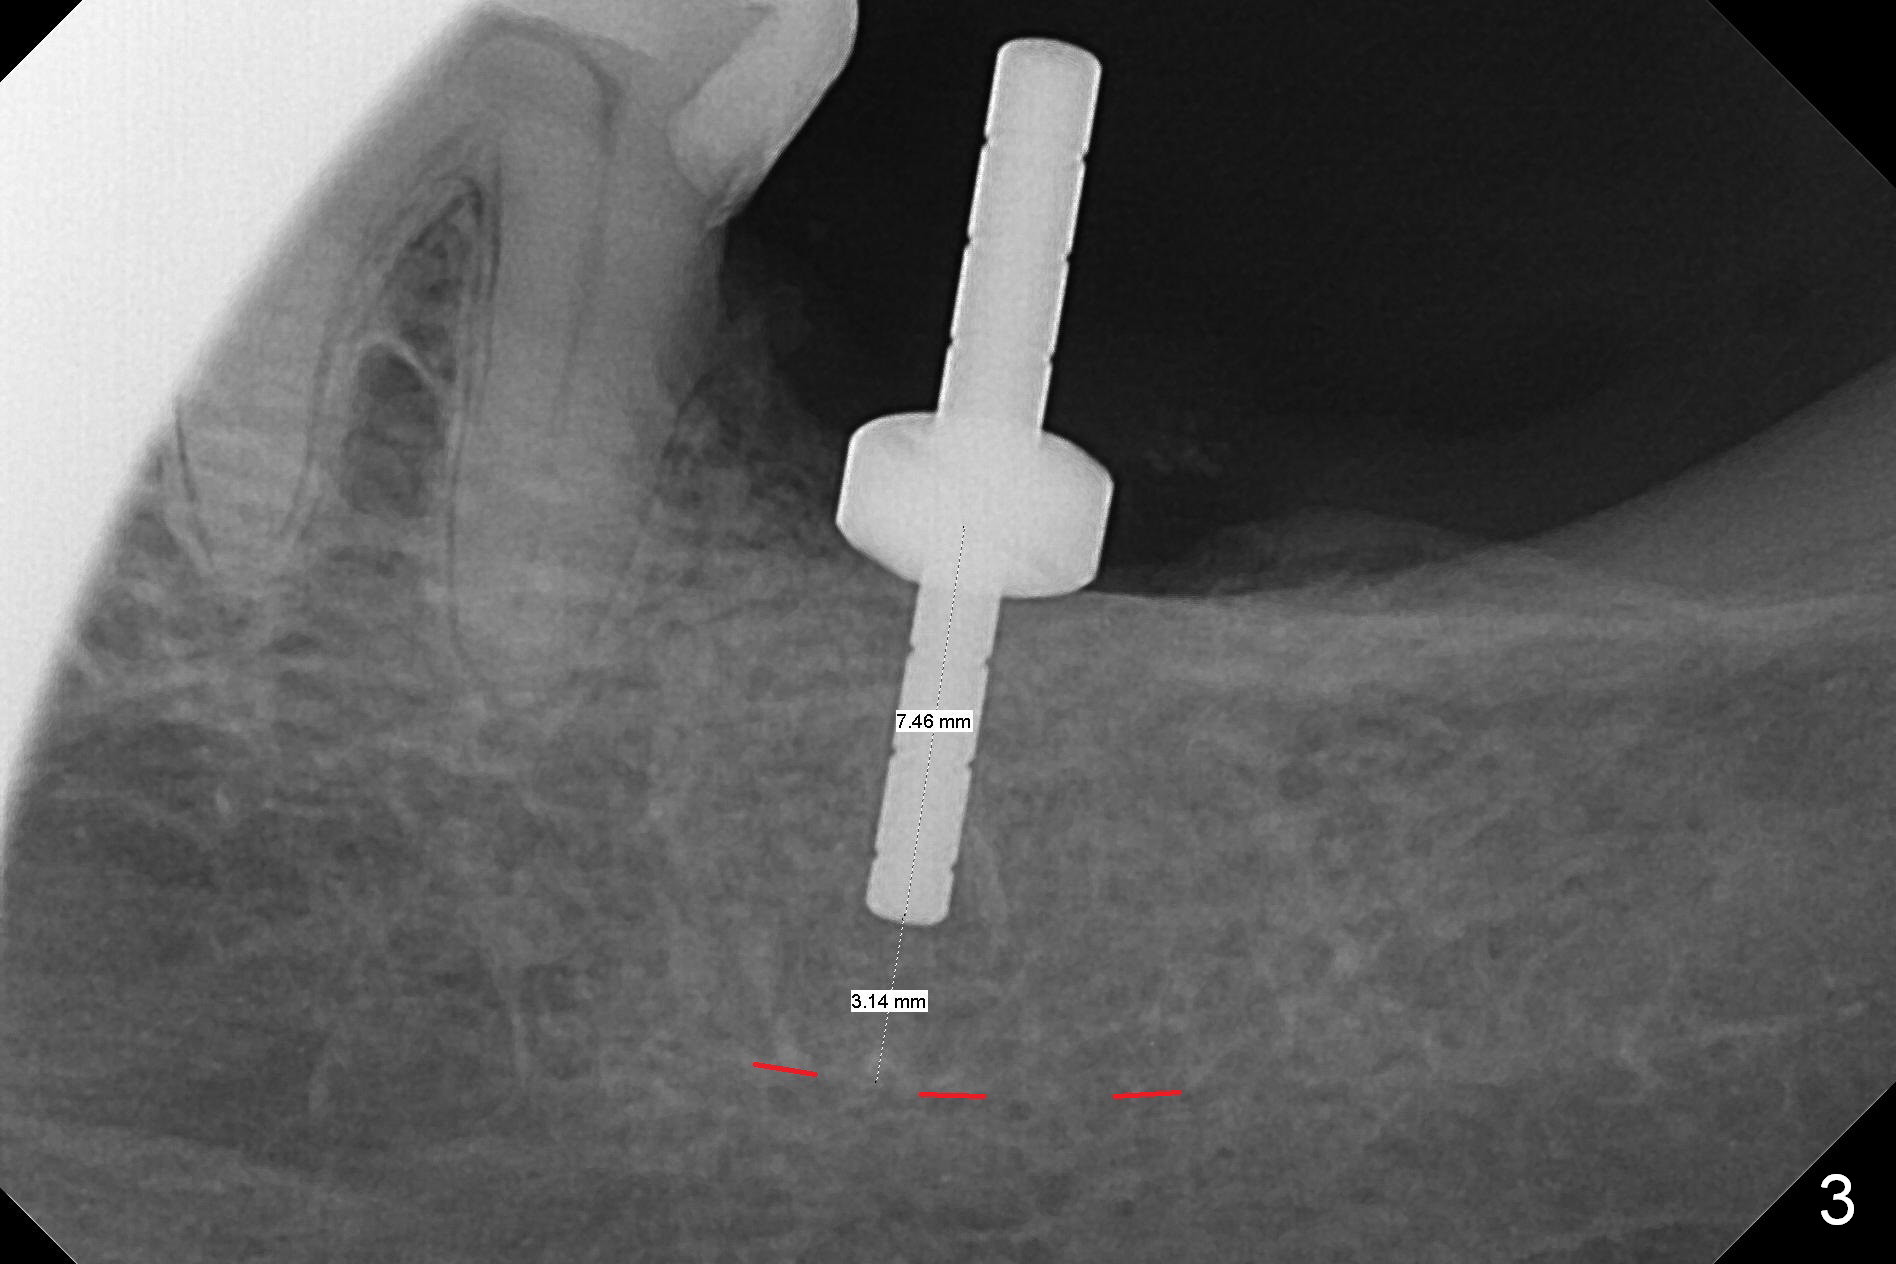

Preop palpation of the edentulous area at #18 does not show the flatness of the ridge top as shown by CBCT.  Incision reveals that the ridge is not as wide as CBCT indicates (Fig.1 (coronal section) between arrowheads).  In fact the ridge is concave (Fig.2 red dashed line).  Osteotomy is initiated in the middle of the concavity (Fig.2 green line) with insertion of 7 mm guide pin (Fig.3).   After removal of the pin, the osteotomy is moved buccally (Fig.4).  After Marking Bur and 4.3 mm Magic Drill, a 5x9 mm IBS implant is placed with 2.8 mm clearance from the Inferior Alveolar Canal (Fig.6).  Following deepening the osteotomy with Final Drill, the implant is placed deeper (Fig.7).  The osteotomy happens to be established in the mesial socket, since the distal socket has not completely healed (Fig.6 yellow dashed line).  Granulation tissue is removed.  Since the lingual crest is lower than the buccal one (Fig.1 B), there is lingual thread exposure after implant placement (Fig.5).  The exposed thread is covered by bone graft (autogenous bone, allograft and Osteogen, Fig.5 pink circles).  Some of the graft is apparently pushed into the distal socket (Fig.7 yellow dashed line) post GBR and suture.  As the implant is placed twice, insertion torque is <10 Ncm (although the implant is stable).  A 5x3 mm healing abutment is placed (Fig.7 H).